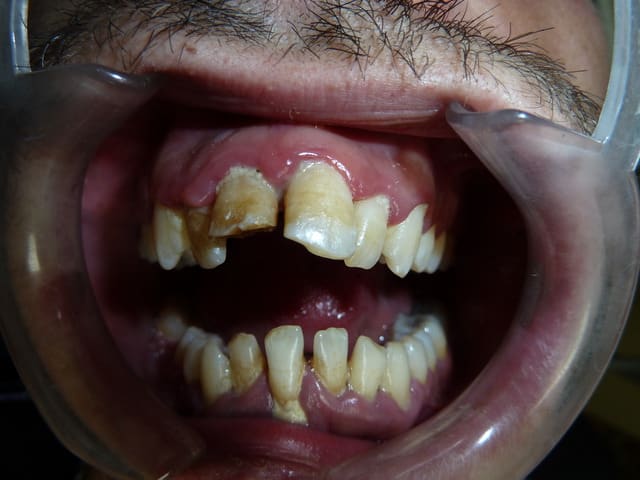

-vous vous êtes brossé les dents avant de venir ?

-ah oui! pendant 3 minutes

(au moins...! et réparti sur 3 semaines)

la prothèse sup , c'est moi qui l'ai nettoyé. imaginez comment elle devait être!